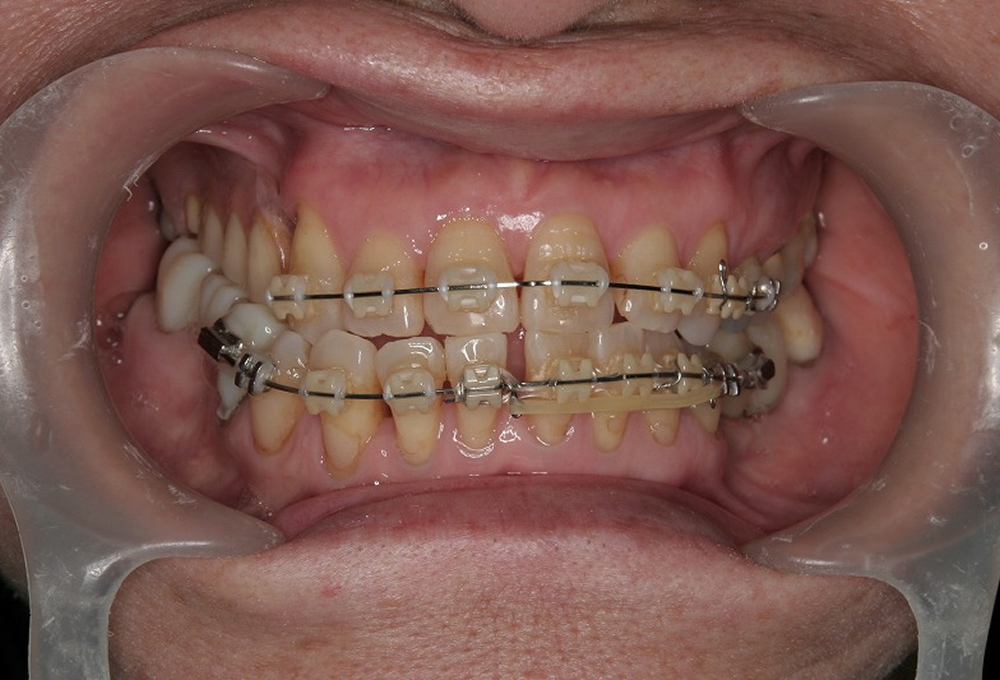

④矯正中